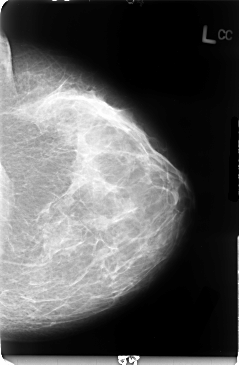

B_3051_1.LEFT_CC

LEFT_CC LINES 4736 PIXELS_PER_LINE 3096 BITS_PER_PIXEL 12 RESOLUTION 50 NON_OVERLAY